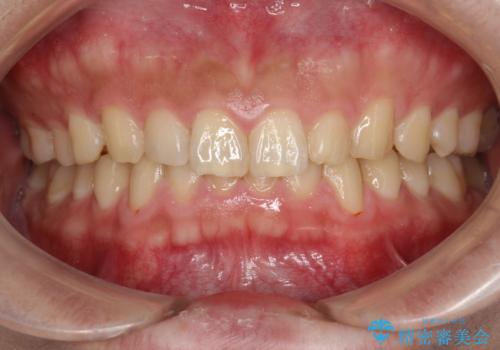

60分のPMTCで歯の黄ばみをきれいに除去

- 年末年始と忙しく、なかなか歯のケアがしっかりできなかった事と着色も気になるとのことで来院されました。PMTC60分コースを行いました。

歯の着色は日常の飲食物などからも付着してしまうことがあります。

代表的に、コーヒーやお茶、赤ワインなどの飲み物、カレー、チョコレート、ミートソースなどが着色しやすいと言われています。